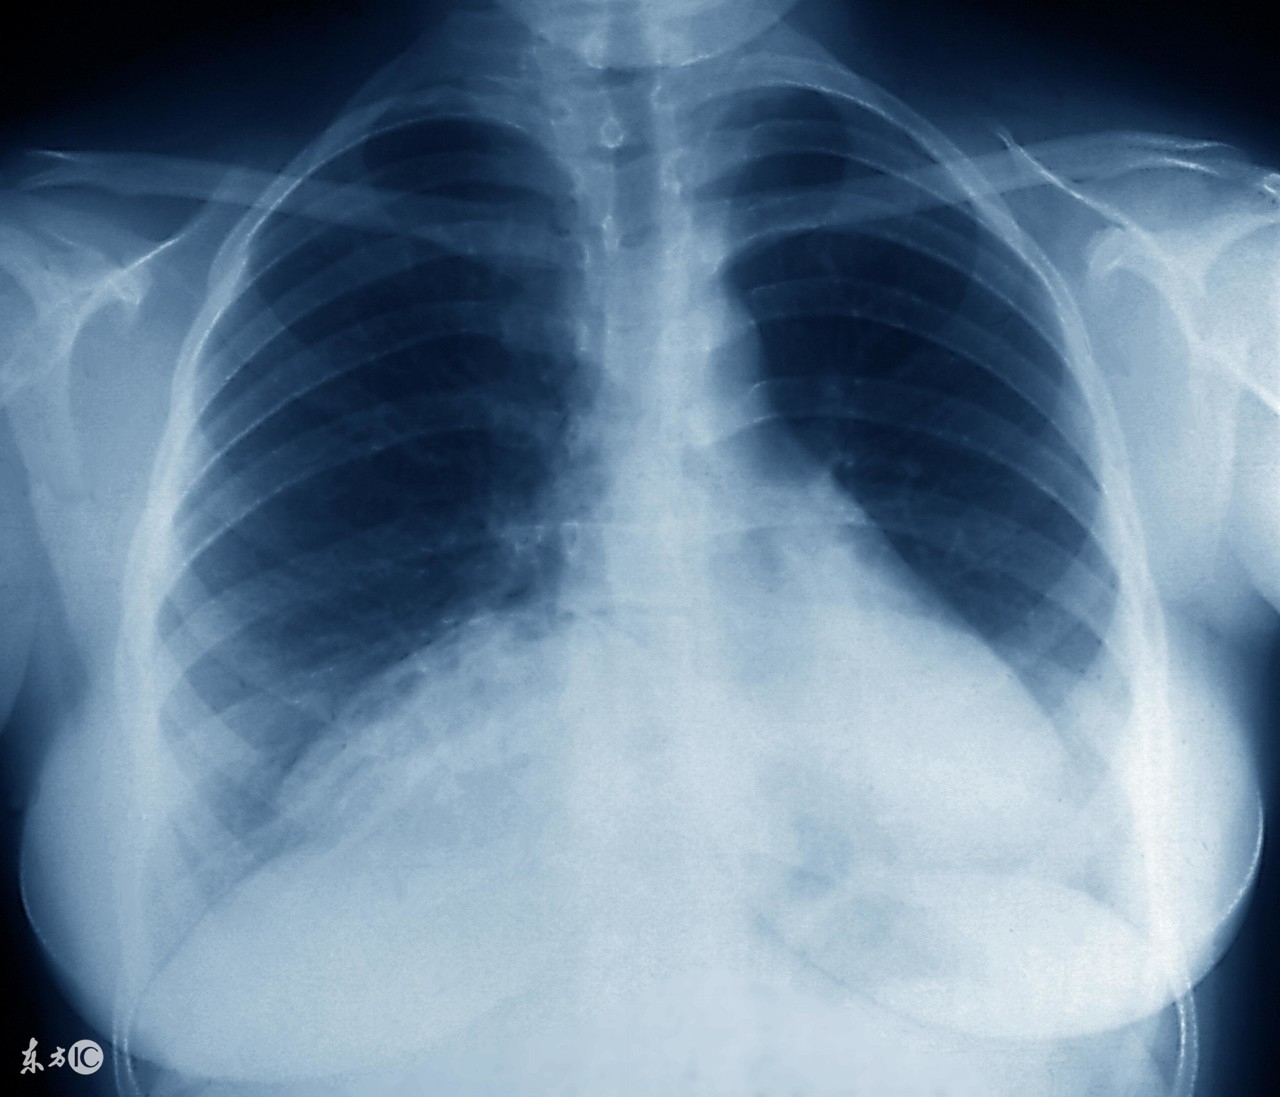

支原体肺炎和其它肺炎疾病一样,是需要及时对症治疗的,支原体肺炎患上之后就引起长期的低烧和畏寒等情况,及时对症治疗才是最关键的,由于治疗不当或是滥用药物都会引起支原体肺炎,面对复发的支原体肺炎,患者要消除病因,利用抗生素抑制病情。那么,支原体肺炎反复发作怎么治疗最佳?下面来了解吧。

必须强调的是,常用于治疗支原体肺炎的青霉素类和头孢菌素类抗生素,其抗菌原理为阻止细胞壁合成。支原体肺炎主要是由于肺炎支原体呼吸道感染而引起的肺部感染,是较为常见的肺部炎症,临床上对于较轻的患者一般可以自愈,较为严重的患者一般用抗菌药物进行治疗,较为常用的药物为大环内酯类药物。